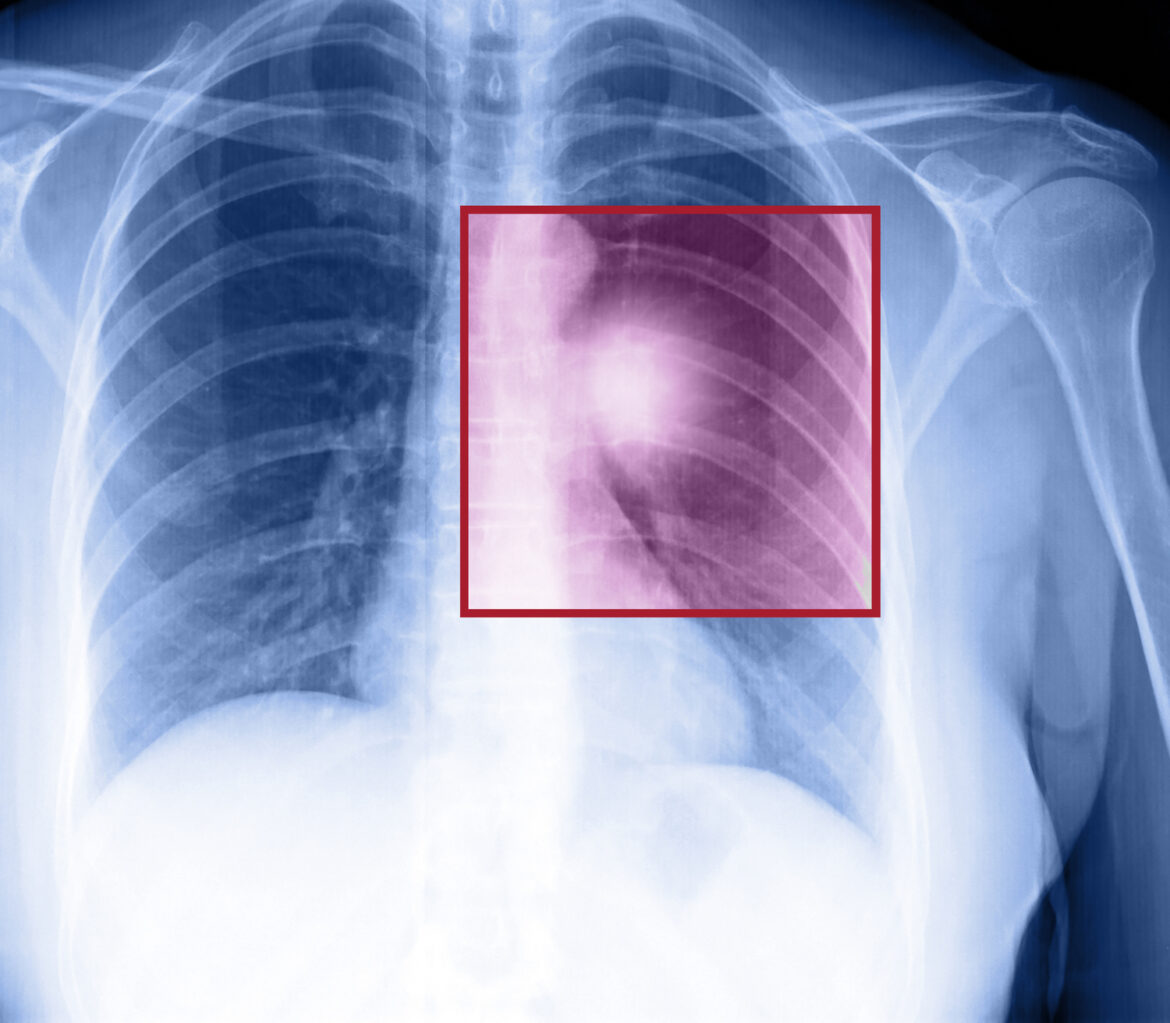

As the cells go on multiplying, they throw everything else off track. The mutated cells may form a mass or lesion on the lung which can be detected by a chest X-ray or a CT scan. A mass is either benign or malignant.